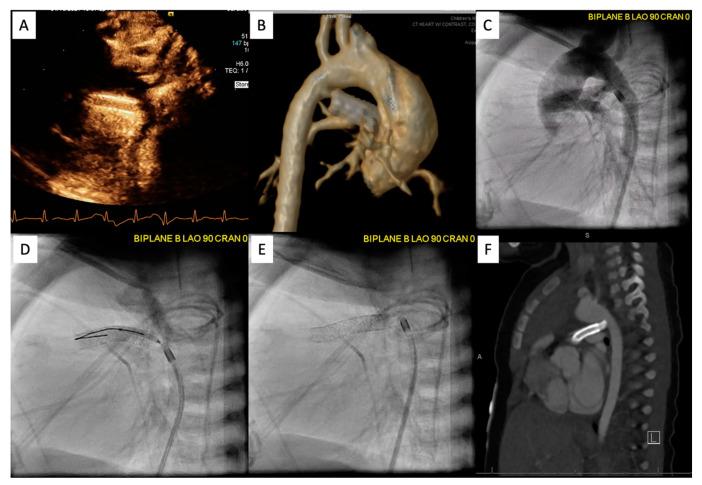

Management of congenital heart disease (CHD) has recently increased utilization of cross-sectional imaging to plan percutaneous interventions. Cardiac computed tomography (CT) and cardiac magnetic resonance (CMR) imaging have become indispensable tools for pre-procedural planning prior to intervention in the pediatric cardiac catheterization lab. In this article, we review several common indications for referral and the impact of cross-sectional imaging on procedural planning, success, and patient surveillance.

先天性心脏病(CHD)的管理最近增加了对横断面成像的利用,以规划经皮介入治疗。心脏计算机断层扫描(CT)和心脏磁共振(CMR)成像已成为小儿心导管实验室介入治疗前程序规划中不可或缺的工具。在本文中,我们回顾了转诊的几个常见指征以及横断面成像对程序规划、成功率和患者监测的影响。